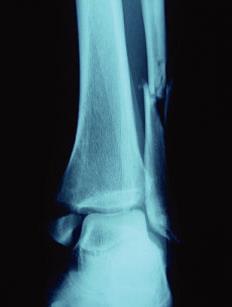

Quel est le diagnostic concernant la fracture de cheville sur cette radio? Quel est le mécanisme lésionnel probable?

Fracture bimalléolaire de cheville sus-tuberculaire

mécanisme en aBduction forcée